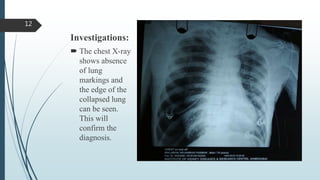

Investigations:

 The chest X-ray

shows absence

of lung

markings and

the edge of the

collapsed lung

can be seen.

This will

confirm the

diagnosis.